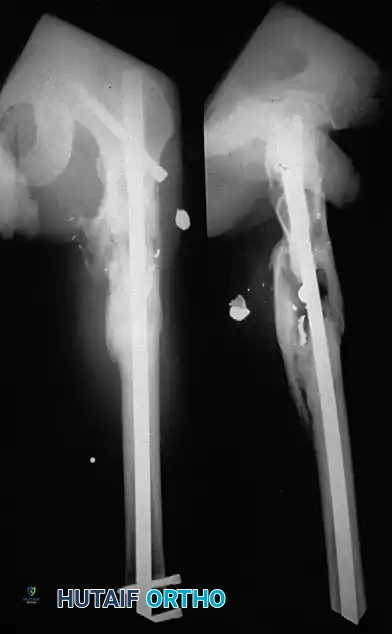

Intramedullary Nailing vs. Casting

Locked intramedullary (IM) nailing is currently the preferred treatment for most diaphyseal tibial shaft fractures requiring operative fixation.

Bone et al. retrospectively compared IM nailing and cast treatment for isolated displaced tibial shaft fractures. Nonunions occurred in only 2% of nailed fractures compared to 10% of casted fractures. Furthermore, 10% of casted fractures healed with unacceptable malalignment, whereas none of the nailed fractures did. Puno et al. and Hooper et al. corroborated these findings in prospective trials, demonstrating superior union rates, lower malunion rates, and faster return to work with IM nailing.

Postoperative Protocol and Complications

Postoperative management is dictated by the fracture pattern, soft-tissue envelope, and the stability of the chosen fixation.

For intramedullary nails in stable patterns, immediate weight-bearing as tolerated is often permitted. For circular frames, weight-bearing is encouraged to promote micromotion at the fracture site, which stimulates secondary bone healing (callus formation). Meticulous pin site care is mandatory to prevent superficial infections

Associated Surgical & Radiographic Imaging